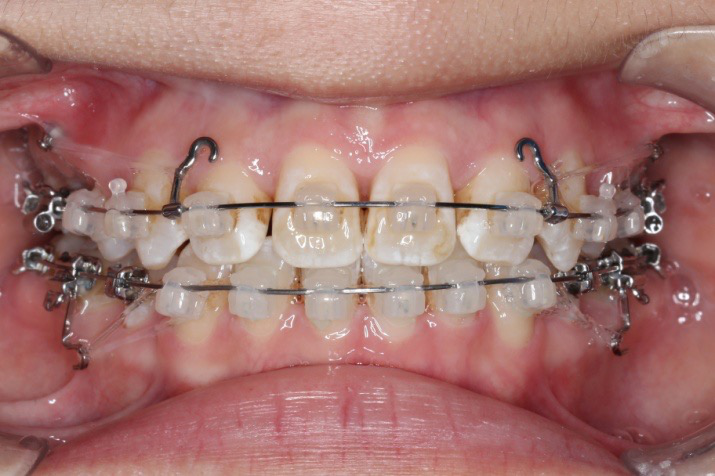

2016.10.31  初戴,0.013cu-niti2017.1.13  上颌加TPA,U56间斜形植入韩国庆北1312-08种植钉,上下0.16cu-niti

2017.02.16  上下0.014*25 cu-niti,50g 拉尖牙远中

2017.04.28

2017.04.28  上0.016*25ss 13、23近远中约5度 v形曲,下0.017*25ss

2017.05.26  磨牙近中倾斜,下颌36、46加power arm

2017.07.25

2017.07.25  上前牙加颈部弹力线